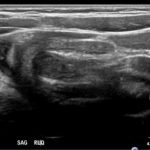

The patient’s abdominal ultrasound revealed intussusception in the right upper abdominal quadrant. The transverse ultrasound view showed a “doughnut sign” (dashed yellow line), telescoping bowel (yellow arrow), and invaginated hyperechoic mesenteric fat with crescent configuration (dashed orange line). The sagittal ultrasound view demonstrated the intussusception formed by the outer recipient bowel loop (yellow arrows), invaginated hyperechoic mesenteric fat (orange asterisks), and telescoping bowel centrally (red arrow).

Ultrasonography should be the initial imaging modality in cases with clinical suspicion for intussusception.4 Previously, contrast enemas were often used as a diagnostic tool and treatment modality. Studies have demonstrated that the modality choice had been related to age, with infants less than six months more likely to undergo enema while children greater than four were more likely to have a computed tomography scan or ultrasound.5 In the pediatric population, ultrasound has a sensitivity of 97.9% and specificity of 97.8% for diagnosis of ileocolic intussusception.6 A “doughnut,” “pseudokidney,” or “target sign” are diagnostic findings.3,7 The study could be performed by radiology or at the bedside in the ED.8,9 A study reported that with limited training, ED physicians could accurately perform ultrasound to diagnose intussusception, with a sensitivity of 85% and a specificity of 97%. Further studies are needed to determine the utility of bedside ultrasound for the diagnosis of intussusception in the community setting.3